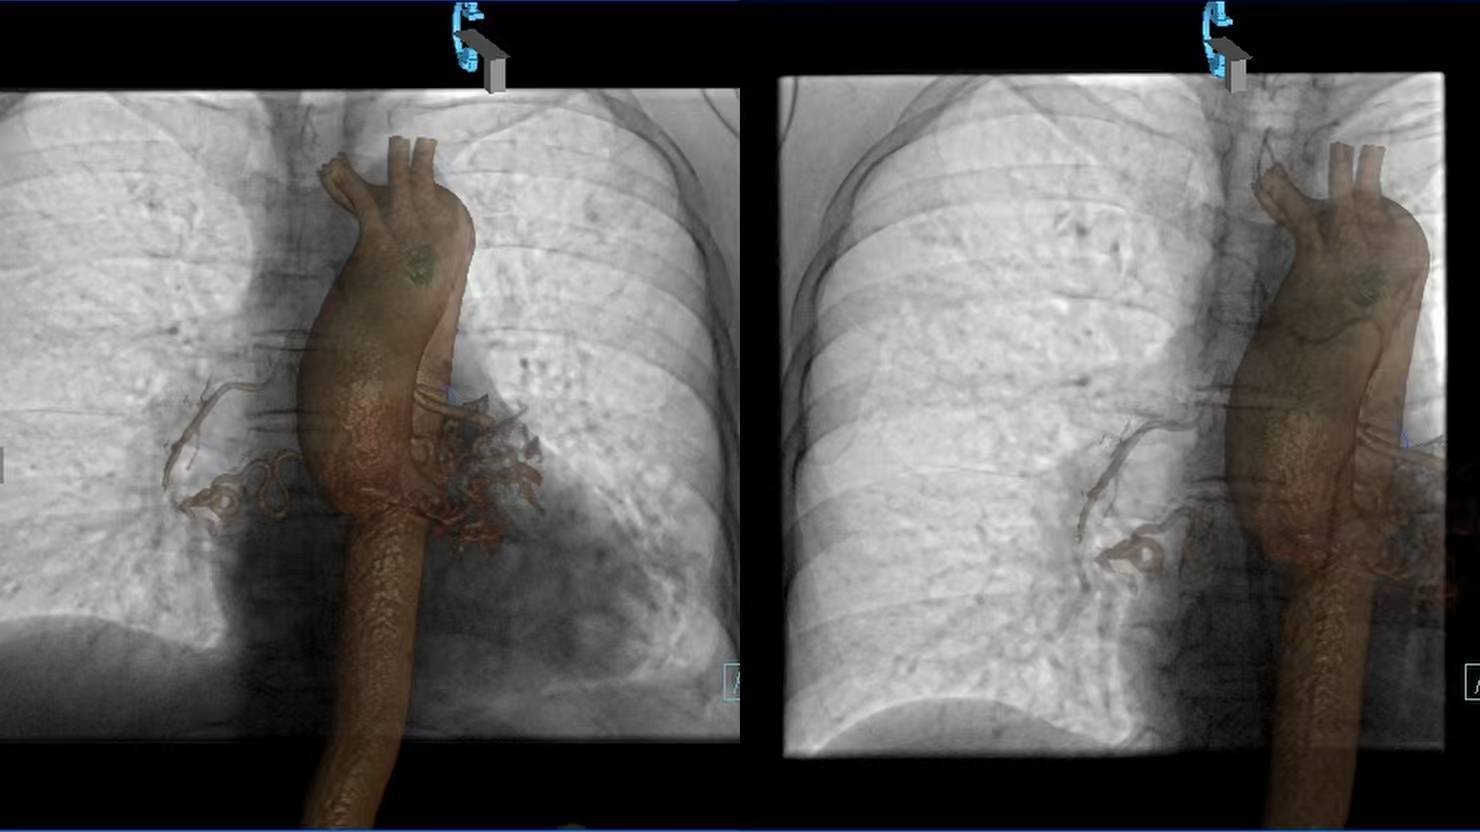

3天前,冯阿姨晨起咳痰见血丝,没成想很快发展成大口咯血。家人将冯阿姨紧急送往西安大兴医院渭水园院区后,术前CTA检查显示其支气管动脉严重迂曲扩张,术中更发现支气管动脉-静脉瘘——这正是咯血的“元凶”。

术前CTA与术中DSA影像精准配准,3D Fusion技术让迂曲血管立体呈现,Overlay技术将血管走形叠加在实时画面上——原本“盲探”的出血点,瞬间“一眼锁定”。微导管在导航引导下快速且精准到达靶血管,快速注入栓塞剂顺利止血。从麻醉到手术结束,仅用45分钟,较传统手术缩短近2小时。